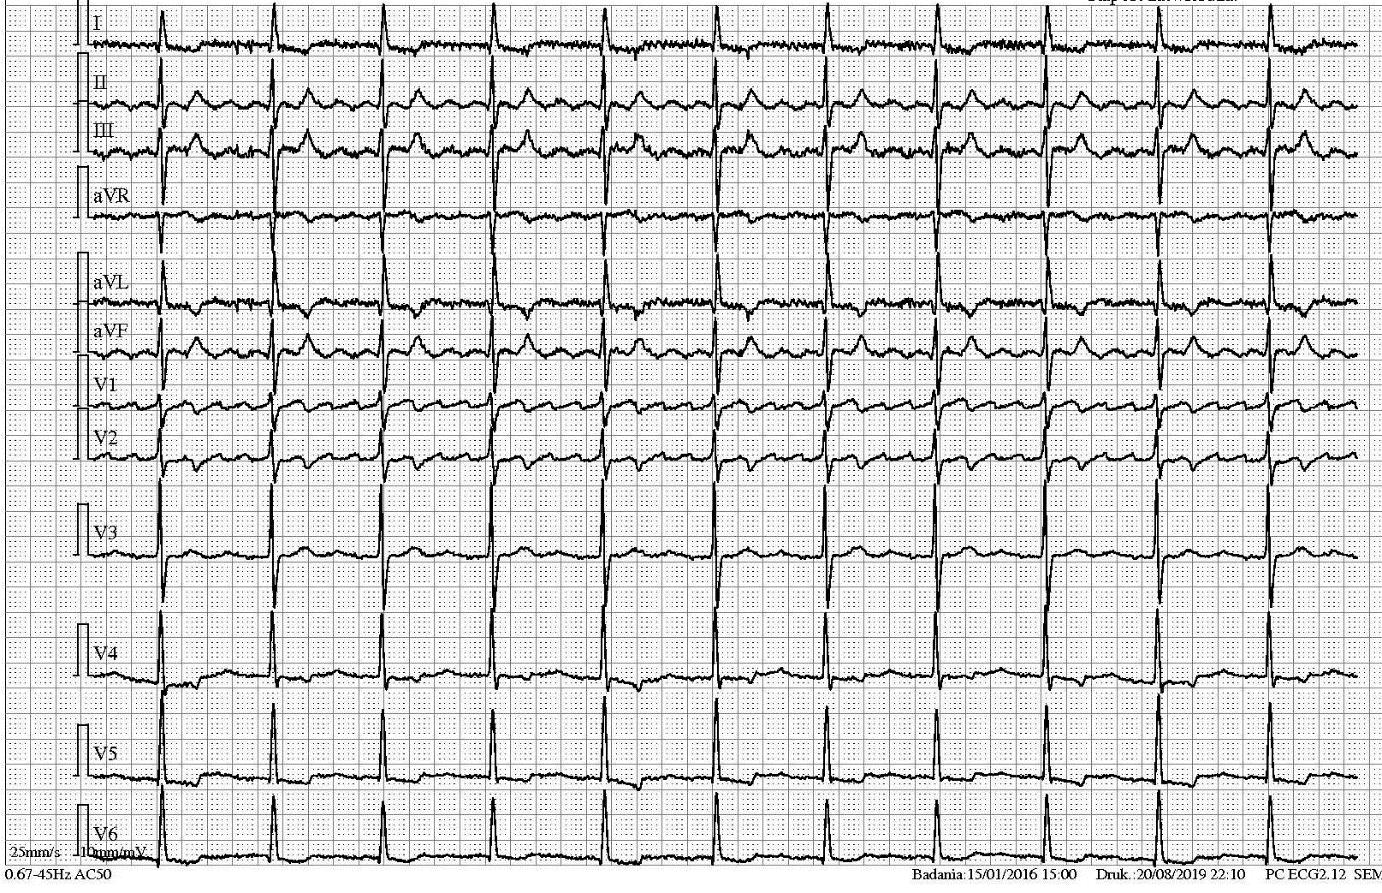

89-letnia kobieta z napadowym migotaniem przedsionków leczona amiodaronem, acenokumarolem i metoprololem od 3 dni jest osłabiona, jeden raz zemdlała, RR 185/80 mmHg. EKG jak na rycinie. Jakie leki należy podać?

87-letni mężczyzna zgłosił się na SOR z powodu urazu głowy. Nie pamięta jakie leki stosuje. INR wynosi 2. EKG jak na rycinie. Wskaż prawdziwe zdanie:

82-letni mężczyzna zgłosił się na SOR z powodu uczucia arytmii serca. EKG jak na rycinie. Co należy rozpoznać i jak leczyć?

70-letni mężczyzna zgłosił się na SOR z powodu omdlenia. Ma wszczepiony stymulator. Jaka jama serca jest stymulowana?

70-letni mężczyzna zgłosił się na SOR z powodu silnego, pierwszego w życiu bólu w klatce piersiowej. Nigdy nie miał wykonanego EKG. EKG jak na rycinie. Co należy rozpoznać i jak leczyć?

27-letni mężczyzna, z padaczką, omdleniami, blokiem p-k z czasową stymulacją endokawitarną 66/min. Z powodu okresowej nieskuteczności tej stymulacji endokawitarnej ma założoną również stymulację przezskórną nastawioną na stymulację 40/min. Co pokazuje pierwsza od lewej strzałka oznaczona literą A?

68-letni mężczyzna zgłosił się na SOR z powodu kołatania serca. Ma wszczepiony stymulator. EKG jak na rycinie. Co należy rozpoznać i jak zwolnić częstość serca?